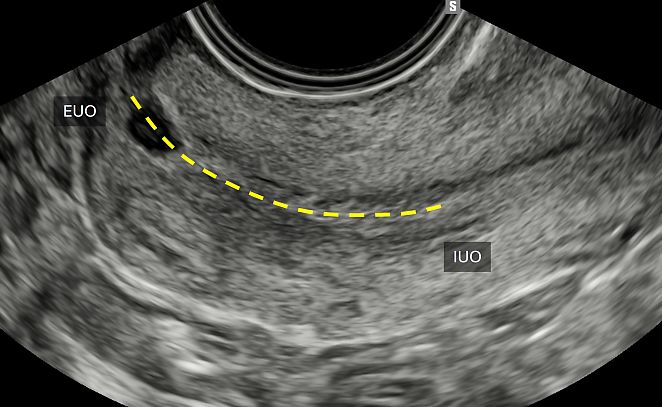

The cervix is a cylindrical organ that protrudes into the vagina and is bounded caudally by the external os or external uterine orifice (EUO) and cranially by the internal os or internal uterine orifice (IUO), which marks the junction between the cervix and the uterine body.8

Through endocavitary ultrasound, either transvaginal or transrectal, the posterior and anterior lips of the cervix and its length can be evaluated, and measurements can be taken from the IUO to the EUO in a longitudinal plane (Figure 2). By examining the cervix in two orthogonal planes, cervical pathology – both benign (e.g. polyps, fibroids) and malignant – can be identified, by focusing on stromal infiltration, vascularization and assessment of tissue elasticity and mobility.

2

Longitudinal scan of the cervix, showing measurement of its length, which is the distance between the external uterine orifice (EUO) and the internal uterine orifice (IUO).